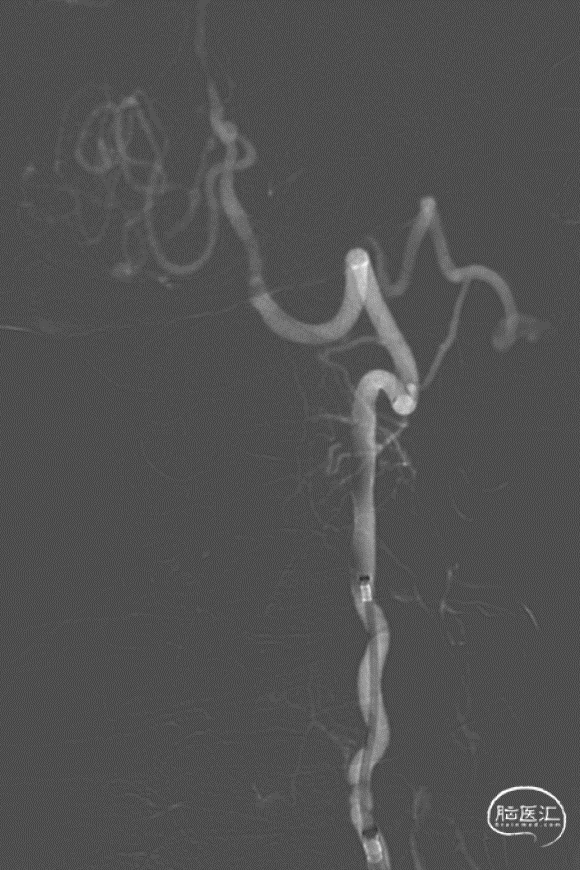

术后造影。

使用加奇生物Fastunnel®输送型球囊扩张导管,无需进行导丝交换、球囊交换以及支架微导管交换的过程。使用“零交换”技术可以减少器械交换,简化操作步骤,降低手术风险,提高手术安全。